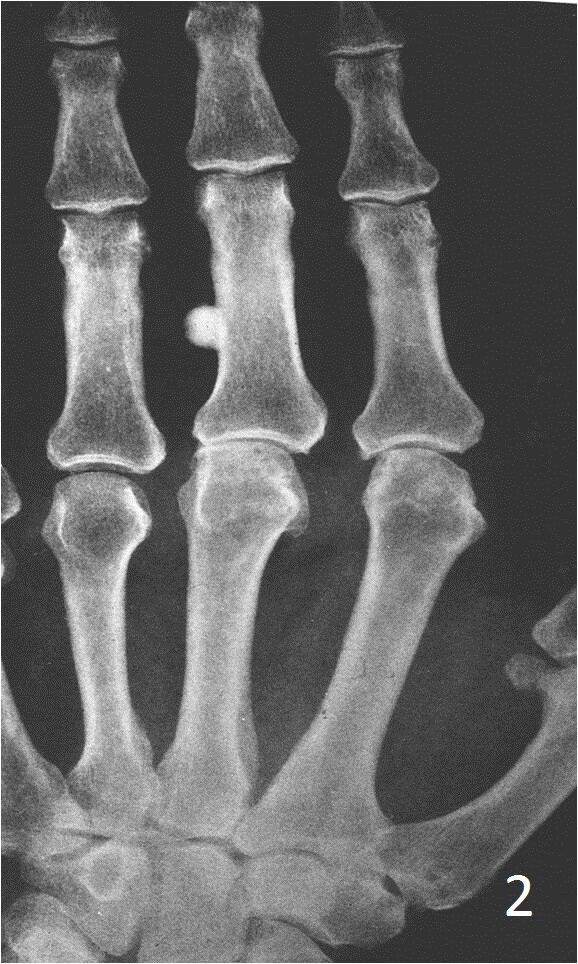

Plain x-ray

• Sharply defined, radiopaque smooth, homogeneous bone protruding from the surface of a bone

• Almost appears as a localized thickening of the bone

Fig. 2. AP xray of hand show a well circunscribed bone lesion on the 3rd index consistent with a small osteoma.